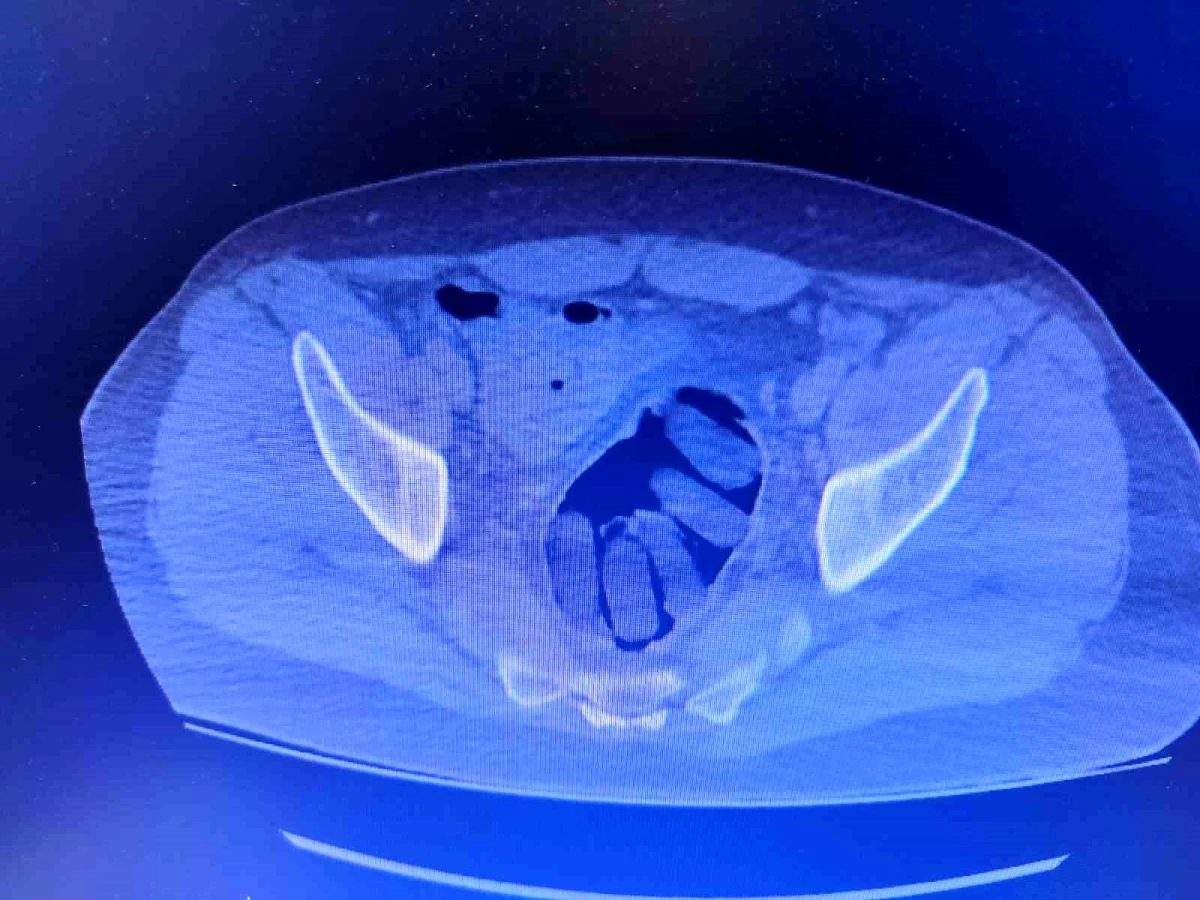

Kırşehir İl Emniyet Müdürlüğü Narkotik Suçlarla Mücadele Şube Müdürlüğü ekipleri tarafından yapılan çalışmalarda yabancı uyruklu Y.S. ve H.S.’nin doğu illerinden ülkeye kaçak yollarla girdikleri ve batı illerine uyuşturucu madde kuryeliği yaptıkları tespit edildi. Takibe alınan uyuşturucu kuryelerinin seyahat ettiği yolcu otobüsü Kırşehir’de durduruldu. Gözaltına alınan ve hastaneye götürülen şahısların midelerinde kapsül bulunduğu tespit edildi. Şahısların midelerinde zulaladığı 126 kapsül halinde 1 kilo 300 gram ve 44 kapsül halinde 550 gram uyuşturucu madde ele geçirildi.